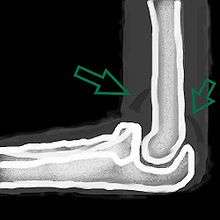

| A traumatic right knee effusion. Note the swelling lateral to the kneecap as marked by the arrow. | |

A joint effusion is the presence of increased intra-articular fluid.[1] It may affect any joint. Commonly it involves the knee.